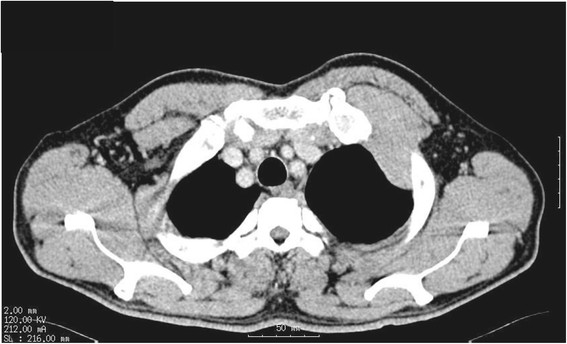

A 58-year-old Japanese man was admitted with left chest pain. He worked in the electrical industry for 40 years. Chest radiography revealed left pleural effusion and a 6-cm diameter protruding tumor on the anterior chest wall. A needle biopsy pathologically confirmed epithelioid-type MPM. Computed tomography revealed direct intercostal invasion of mesothelioma between the first two ribs (Figure 1). Preoperative OK-432 (PicibanilTM, Chugai Pharm. Co. Ltd., Tokyo, Japan) was administered twice (total 3KE) intrathoracically to promote adhesion between the visceral and the parietal pleura. We decided to perform EPP on consultation with the patient, following a diagnosis of clinical T3N0M0 stage III MPM based on the International Mesothelioma Interest Group classification.

Figure 1.

Preoperative chest computed tomography findings after the drainage of effusion. A chest wall tumor invading the space between the first and second ribs.